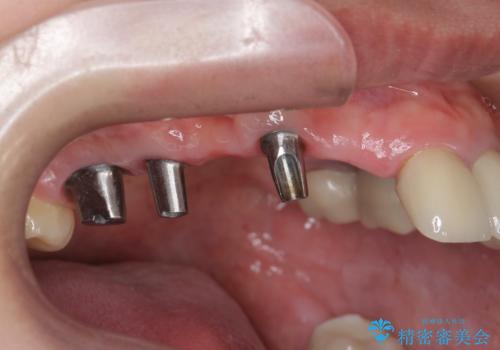

虫歯による多数歯欠損 インプラント咬合機能回復

- 虫歯が多発し、多数失ってしまった歯の審美性回復・機能回復を計画します。

多数の歯が失われておりブリッジは行えないような状況で、インプラント治療か入れ歯治療かを提案しインプラント治療を希望・選択されました。

- 120万円(ストローマンインプラント×3・骨造成・チタンカスタムアバットメント×3・フルジルコニアクラウン×5)費用は治療当時の料金となります